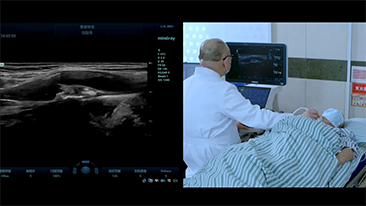

Aparaty ultrasonograficzne z serii Resona, dzi?ki szerokiej gamie za pomoc? wszechstronnych sond do r√≥?nych zastosowaŇĄ i wydajnych narz?dzi do zastosowaŇĄ klinicznych, pomagaj? U?ytkownikom stawia? dok?adniejsz? i efektywniejsz? diagnoz? oraz ocenia? wyniki.

Wspó?czesna rzeczywisto?? medyczna jest bardzo wymagaj?ca. Nieustannie wzrasta liczba trudnych przypadków i nak?adów pracy.